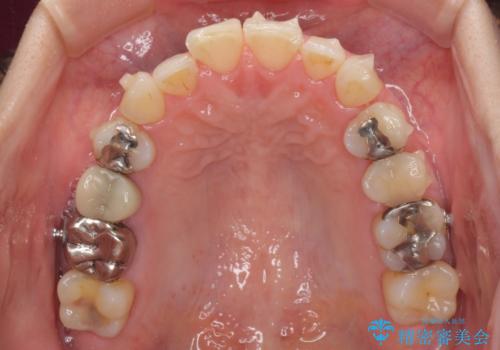

切端咬合をインビザライン矯正で解消

- 前歯のデコボコを気にして来院された患者様です。

上下前歯の先端同士が接触する切端咬合であったため、上顎は歯列を拡大し、下顎はIPR(歯と歯の間を削る)により叢生を解消しながら歯列を小さくすることとしました。

治療途中に前歯に歯髄充血を思わせる痛みが認められたため、無理のない歯の移動と頻繁な経過観察を行いました。

切端咬合はスムーズに解消され、前歯の負担を軽減させることができました。